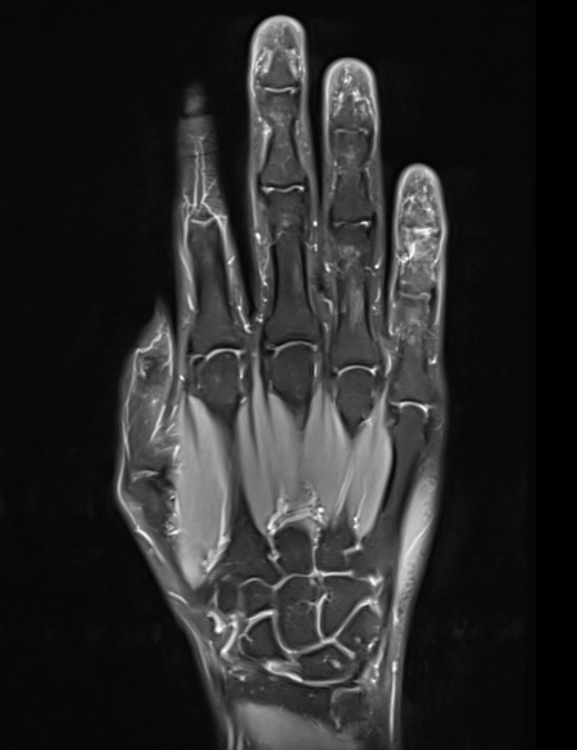

Ich wollte wieder ein Update geben. Und zwar war ich heute Morgen beim Radiologen und habe mir ein privat bezahltes MRT der rechten Hand machen lassen.

Die gute Nachricht ist, dass die Gelenke mit Ausnahme der Endgelenke soweit alle gut aussehen und es keine Wassereinlagerungen usw. gäbe. Was etwas verwunderlich war, ist die Tatsache, dass ich wohl Recht viele Kapilargefäße hätte. Am Zeigefinger ganz deutlich zu sehen, an den anderen Fingern auch vermehrt feststellbar. Dass es am Zeigefinger aufgrund der Psoriasis ist, sei möglich. Die anderen Finger sind ja bei der rechten Hand aber soweit unauffällig, nur dass hier und da vereinzelt die Gelenke zwicken.

Vielleicht ist das in den Gelenken auch eine Überlastung durch die Computerarbeit und vielen Handytippen und erklärt deshalb die Beschwerden.

Trotzdem interessant, wieso die Durchblutung da stärker sei, obwohl meine Finger ja meistens kalt sind 😂

Hier noch die MRT Bilder als Auszug für den interessierten Leser: